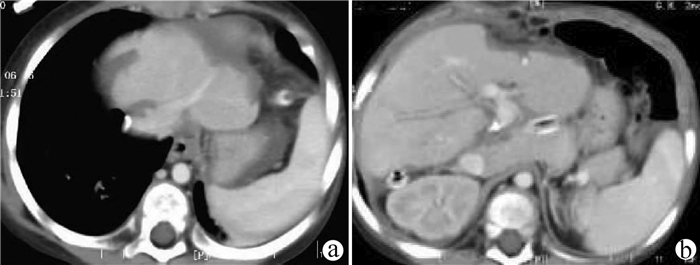

高原地区体外肝切除联合自体肝移植术治疗晚期肝泡型包虫病的术后并发症及其防治策略

田青山, 冯少培, 郭亚民, 韩秀敏, 赵顺云, 叶成杰, 安永德, 吴世乐, 王向前, 郑海波, 朱文君, 阿吉德, 高伟, 潘洪帅

2021, 37(9): 2153-2160. DOI: 10.3969/j.issn.1001-5256.2021.09.029

摘要(1294) HTML (489) PDF (3321KB)(55)

摘要:

目的  探讨高原地区体外肝切除联合自体肝移植术治疗终末期肝泡型包虫病的术后并发症并探讨防治策略。  方法  收集青海省人民医院2013年1月— 2019年3月接受自体肝移植术的11例终末期肝泡型包虫病患者的手术资料及随访资料,对术中及术后情况进行分析。  结果  11例患者均成功行自体肝移植术,无术中死亡,其中2例(18.18%)行半离体肝切除,9例(81.82%)行全离体肝切除。肝后下腔静脉重建方式中,采用自体大隐静脉进行重建者2例(18.18%),采用人造血管重建者4例(36.36%),5例(45.45%)保留自体肝后下腔静脉。胆道重建方式中,8例(72.73%)行胆肠吻合术,3例(27.27%)行胆管端端吻合术。11例患者的术后并发症主要有出血2例(18.18%);胆汁漏、腹腔感染4例(36.36%),胆肠吻合口狭窄1例(9.09%), 血栓2例(18.18%),肺部感染、胸腔积液2例(18.18%);包虫复发1例(9.09%)。11例患者发生围术期死亡2例(18.18%),其余9例(81.82%)患者均好转出院。  结论  出血、胆道并发症和感染是造成高原地区自体肝移植患者死亡的主要原因,精准把握手术适应证、术前仔细多学科评估、术中精湛的操作、外科技术流程的标准化及精细的围术期管理是降低自体肝移植术围术期病死率、避免和减少术后并发症以及使患者获得长期良好生存的关键。